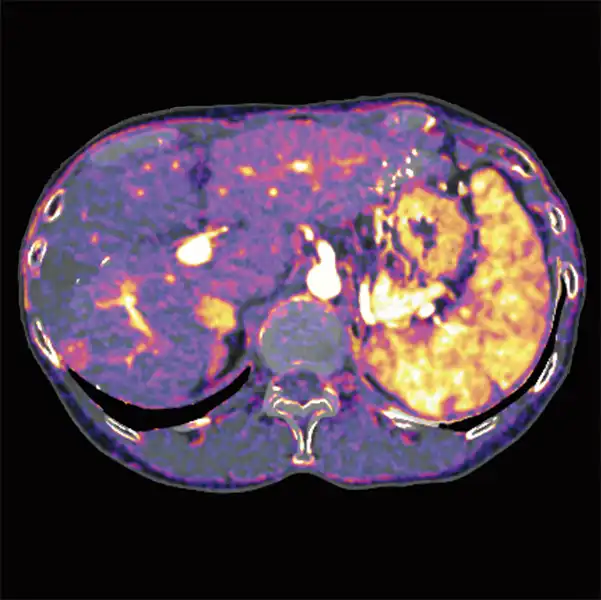

Enhance your diagnostic capabilities with color iodine maps provided automatically for any multiphase abdominal protocol.

Tissue visualization with easy-to-use Dual Energy scanning.